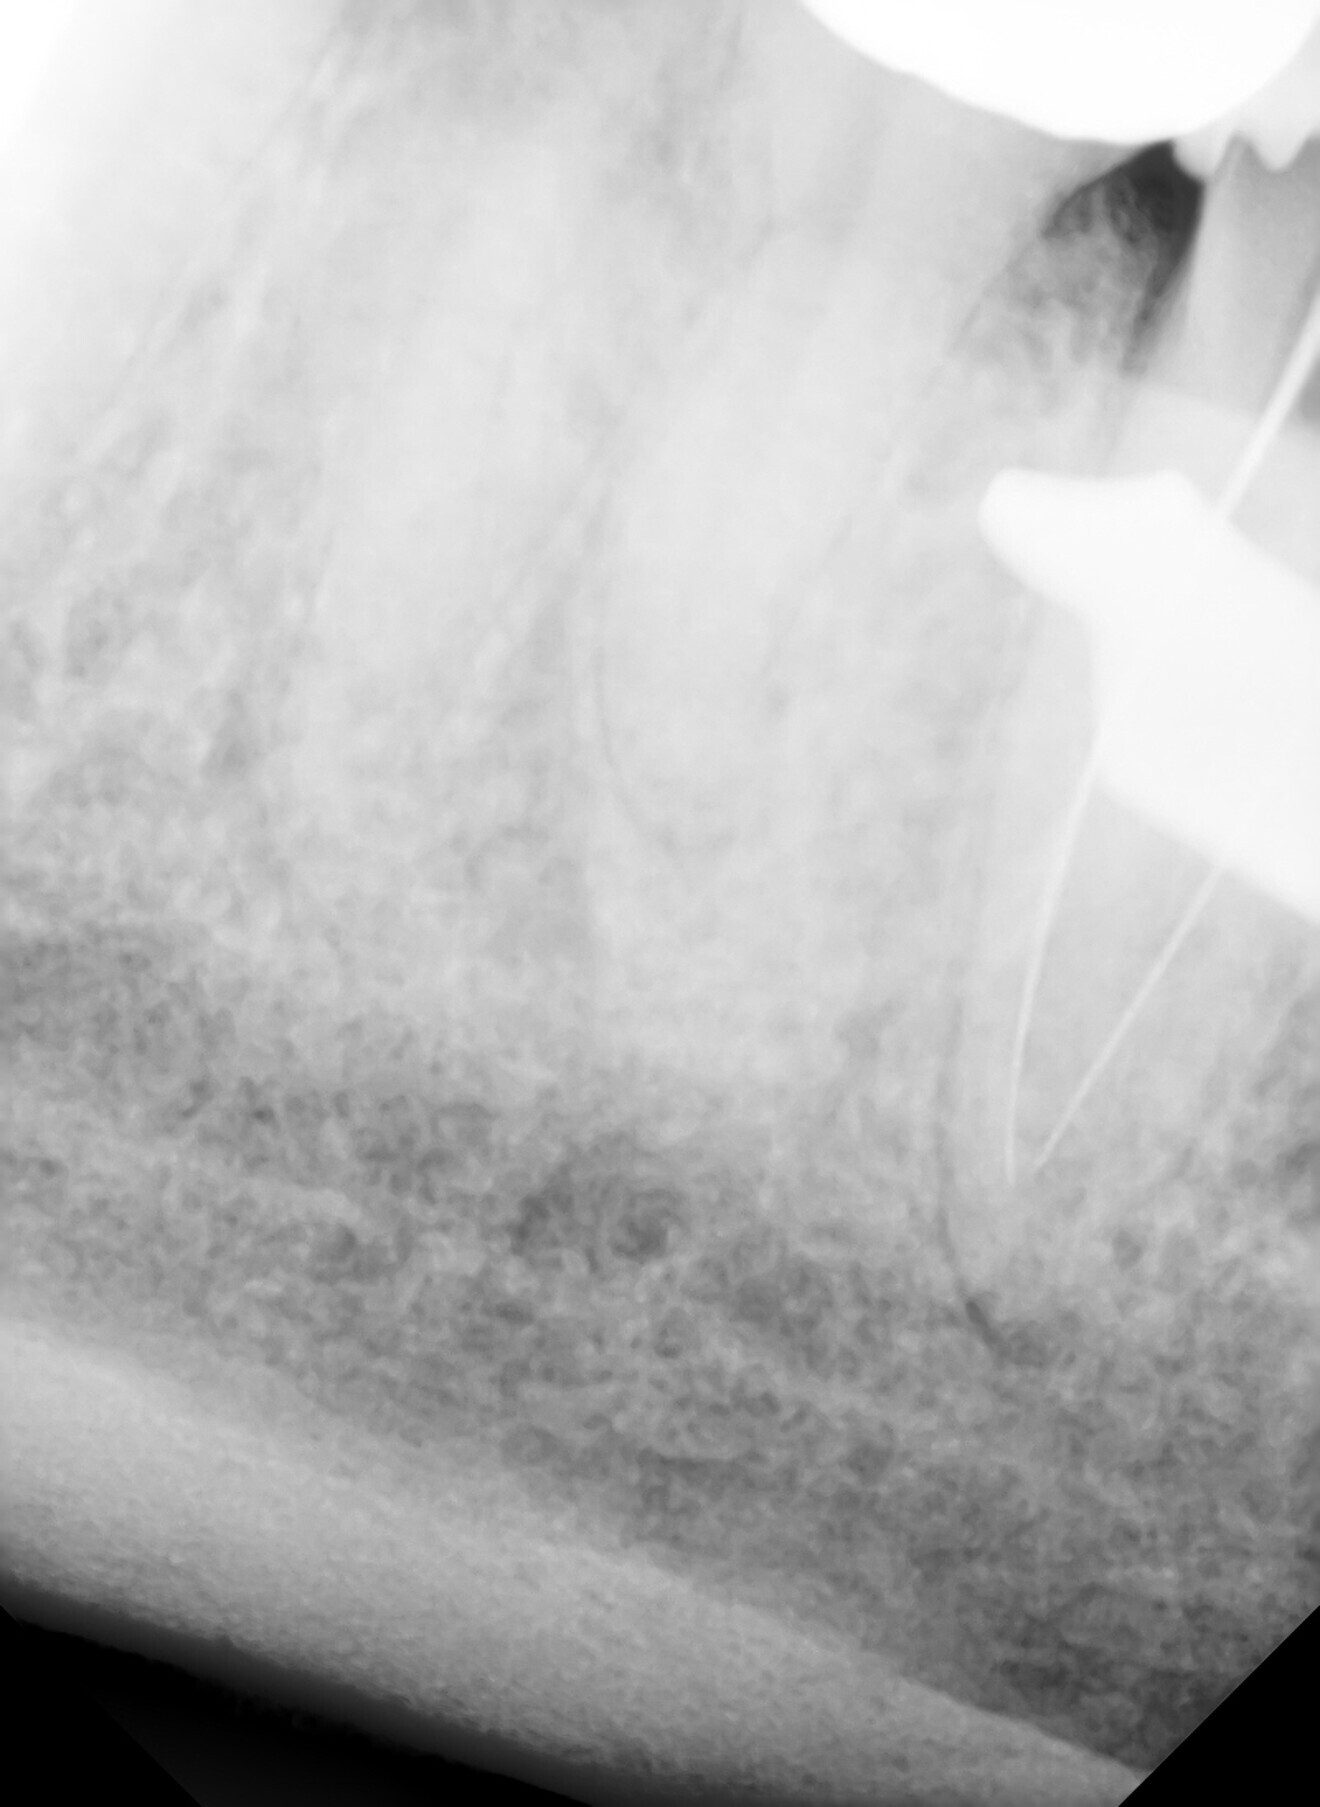

The immediate postoperative radiograph showed that the ceramic sealer cement had been able to penetrate and fill the lateral canals at the apex (Fig. 4), which was a good indication that cleaning had extended to the intricate canal extensions at the apical section of the tooth. Additionally, as the amount of initial periapical bone loss was minimal, no fractures were detected beyond the crown of the tooth, and cuspal protection with a crown was arranged for the same day. It was expected that the tooth would resolve without any adverse symptoms and remain comfortable for the long term. The patient reported no pain or swelling after the completion of endodontic treatment in the two days after the procedure. He returned again for routine dental care two months later (Fig. 5) and reported no symptoms since the completion of endodontic treatment. While the adjacent tooth subsequently required endodontic treatment the following year, tooth #37 continued to be comfortable for the patient, and there had been no recurrence of symptoms at the one-year follow-up (Fig. 6).

Fig. 4.

Fig. 5.

Fig. 6.